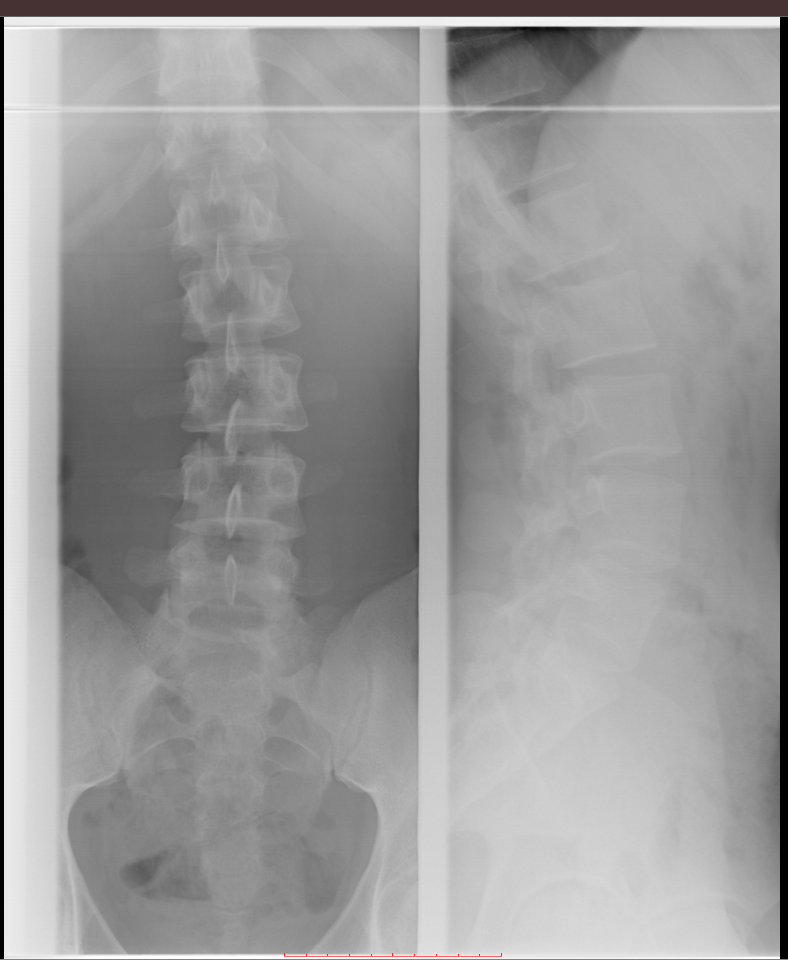

Рентгеновские снимки крестцово-копчикового отдела позвоночника